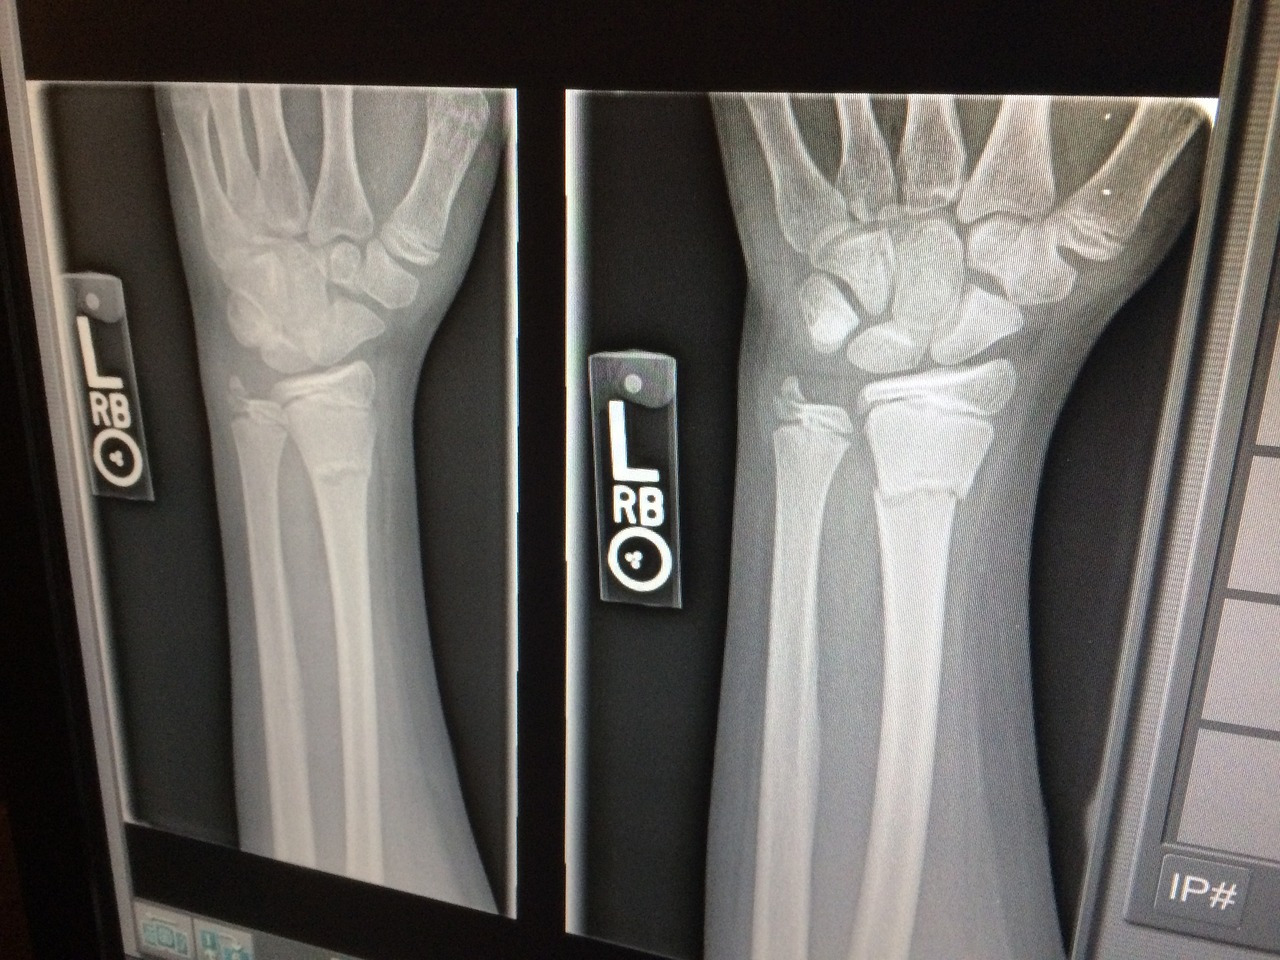

엑스레이도 찍고 팔도 이리저리 굽혔다 펴본다.

"엑스레이에서는 특이한 사항은 없어요. 요즘 뭐 팔을 무리하게 쓰신 적이 있으세요? 운동이라던지."

어리석은 테니스 새싹은 테니스 이야기가 나오면 치지 말라고 할까 봐 거짓말 대신 말을 아끼는 것을 선택했다. 일단 팔을 최대한 쓰지 말고, 염증약을 처방해 줄 테니 먹어보고 그래도 증상이 낫지 않으면 5일 후에 다시 오라고 한다.